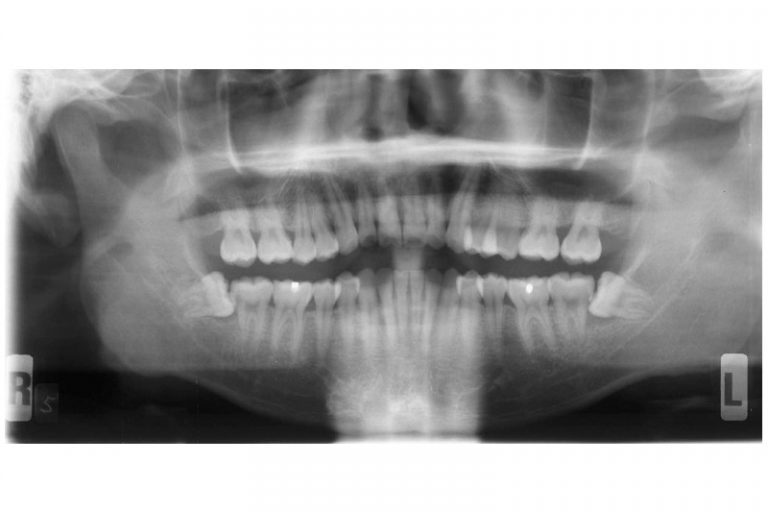

全口X光片顯示 下顎左右有阻生智慧齒

即使沒有症狀,也有隱藏問題,所以應該定期找牙醫檢查,若出現隱藏的問題,就算不痛亦應拔除智慧齒。阻生等可能會導致牙周病或蛀牙, ,令旁邊本來有用的大牙或其牙骨缺損,但當患者開始疼痛的時候才處理已經太遲。因此建議在18至20歲左右前往牙醫診所檢查並拍攝一張X光片,判斷是否有阻生並需要剝牙。大部份人的智慧齒也沒有足夠位置長出,在有限的空間下成長會導致阻生,無論它生長的角度如何都可能導致上述口腔的問題。

值得注意的是,智慧齒阻生或令組織病變而形成囊腫,因此別以為不痛不癢便無須理會智慧齒。

智慧齒阻生令顎骨內其他組織病變而形成顎骨囊腫